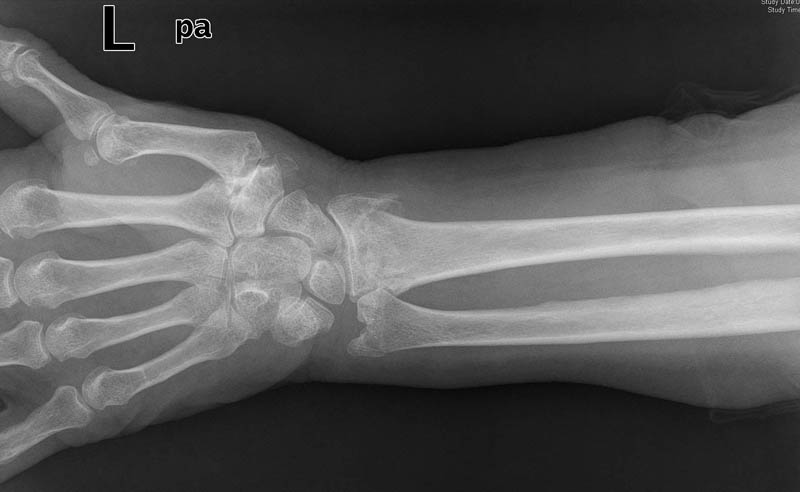

Carpo normal